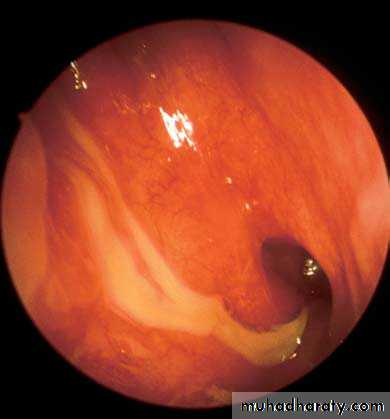

Another diagnostic modality for sinusitis is nasal endoscopyView into left nasal cavity demonstrates a polyp (P) extending from the middle meatus.

p

Purulent discharge from the middle meatus draining into the nasopharynx adjacent to the eustachian tube orifice.

Aspergillus fungal balls of the maxillary sinus. Note the fungal debris and mucosal edema.